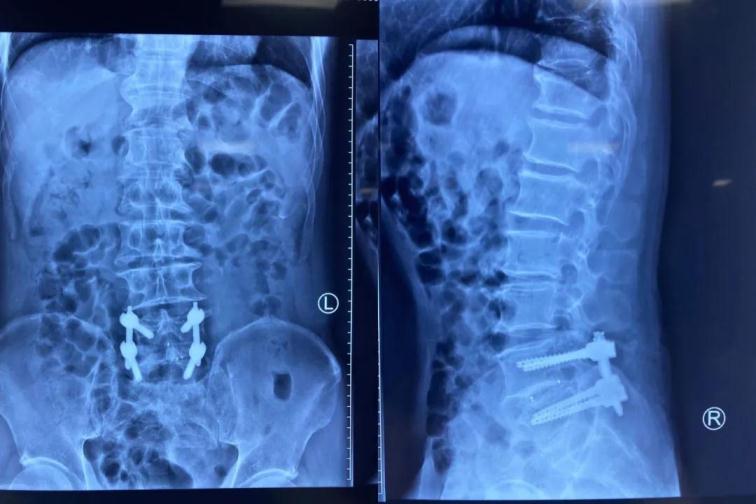

經(jīng)皮椎弓根螺釘內(nèi)固定

術(shù)后復(fù)查

我院骨科已多次成功開展脊柱內(nèi)鏡下經(jīng)椎間孔入路/后路腰椎體融合術(shù)及經(jīng)皮椎弓根釘內(nèi)固定術(shù) (Endo-T/PLIF),此項技術(shù)創(chuàng)傷小、恢復(fù)快,鏡下融合效果確切。本地區(qū)還沒有開展的先例。未來,佳木斯大學宏大醫(yī)院骨科團隊將繼續(xù)努力,讓脊柱微創(chuàng)技術(shù)造福更多三江地區(qū)廣大患者。